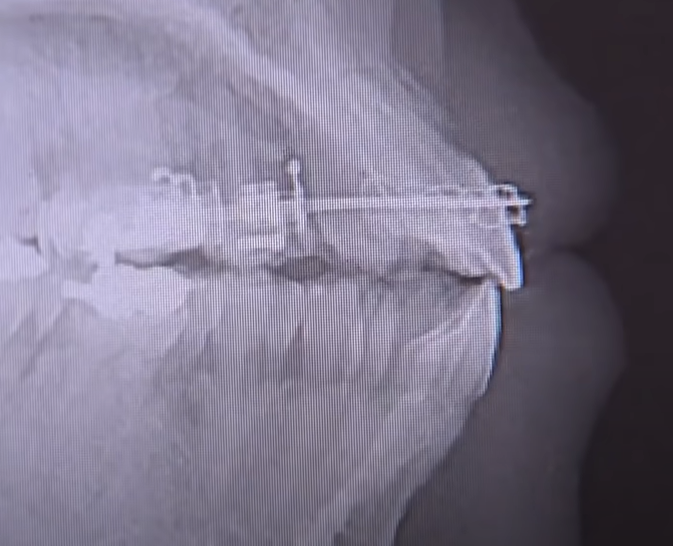

교정 치료 중 잇몸 퇴축 방지

교정 치료는 치아를 이동시키는 과정으로,

이 과정에서 과도한 압력이 잇몸에 가해질 경우 잇몸 퇴축을 유발할 수 있습니다.

교정 치료를 좀 더 천천히 진행하거나 잇몸 퇴축을 미리 예방하기 위한 조치를 취하는 것이 중요합니다.